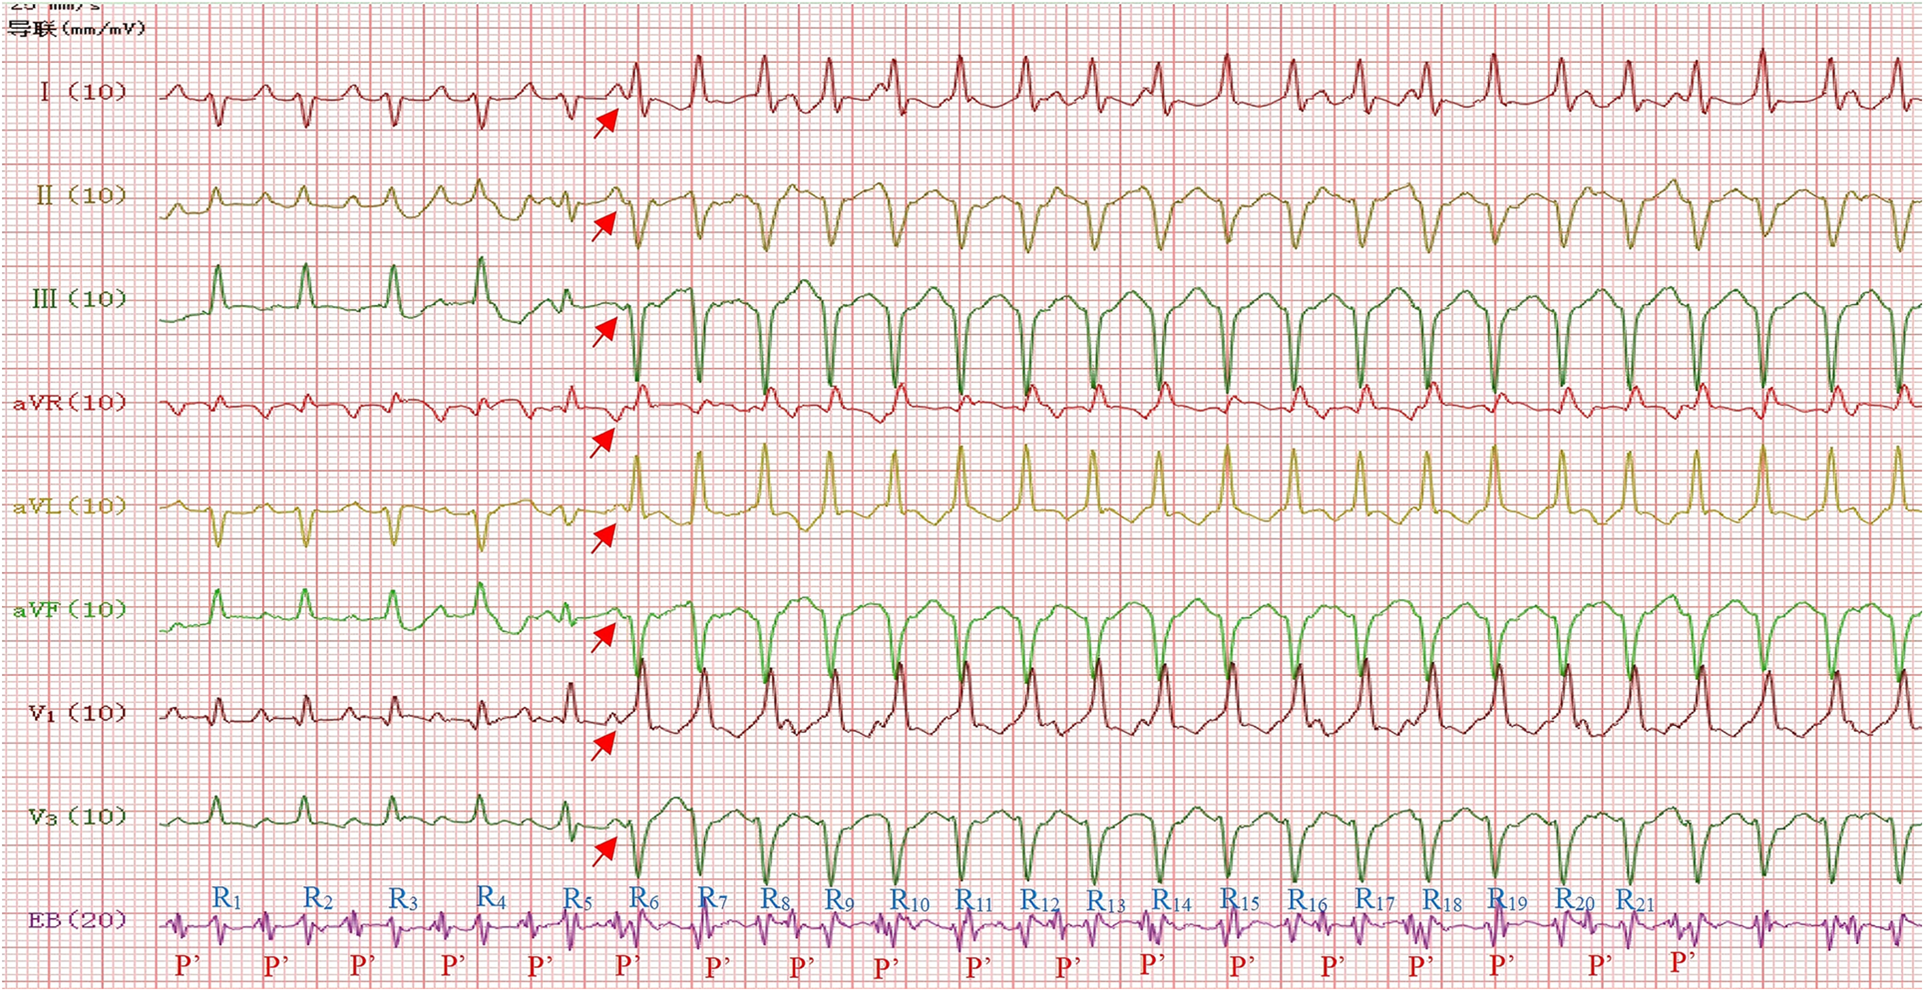

Using the DF-5A cardiac electrophysiological diagnostic and therapeutic instrument produced by Suzhou Oriental Electronic Instrument Factory, a 4-pole esophageal electrode catheter was inserted through the mouth and advanced to 15 cm from the teeth, where the largest atrial wave was recorded. Continuous recordings from the body surface and esophageal ECG showed alternating narrow and wide QRS tachycardia (Figure 2). During narrow QRS wave tachycardia, the ventricular rate was 182 beats per minute (RR interval = 328 ms), with the esophageal lead showing a clear and prominent P' wave that appeared multi-directional, with a P'P' interval of 328 ms, an RP' interval of 176 ms, and a P'R interval of 152 ms. The RP' interval was greater than the P'R interval, which indicated that the P'R interval was prolonged, with the P' wave upright in leads I, II, III, and aVF. During wide QRS wave tachycardia, the ventricular rate was 241 beats per minute (RR interval = 248 ms), with a QRS duration of 74 ms and a QRS axis of −83°. The V1 and aVR leads showed a unidirectional R wave pattern, while the II, III, and aVF leads exhibited an rS pattern, with SIII > SII, suggesting a left anterior fascicular block. The morphology of the P' wave and the P'P' interval were the same as during narrow QRS wave tachycardia, with the ventricular rate exceeding the atrial rate and atrioventricular dissociation, suggesting ventricular tachycardia, where R5 was identified as a ventricular fusion wave. During the recording of the esophageal electrocardiogram, the supraventricular tachycardia stopped on its own, restoring sinus rhythm, with a normal PR interval. Through careful comparative analysis, the P wave in lead III is inverted during narrow QRS complex tachycardia, while it is upright during sinus rhythm (Figure 3). Therefore, the esophageal electrocardiogram confirmed the diagnosis of dual tachycardia (persistent atrial tachycardia combined with short episodes of ventricular tachycardia).

Figure 2

Narrow QRS wave tachycardia: ventricular rate 182 beats/min (RR interval = 328 ms), P’P ‘interval = 328 ms, RP’interval = 176 ms, P’R interval = 152 ms, P’upright in leads I, II, III, aVF,V1,V3 and P’inversion in lead aVR (Red arrow). Wide QRS wave tachycardia: ventricular rate 241 beats/min (RR interval = 248 ms), QRS duration 74 ms, QRS electrical axis −83°, R5 was identified as a ventricular fusion wave. EB = Esophageal Bipolar Lead.